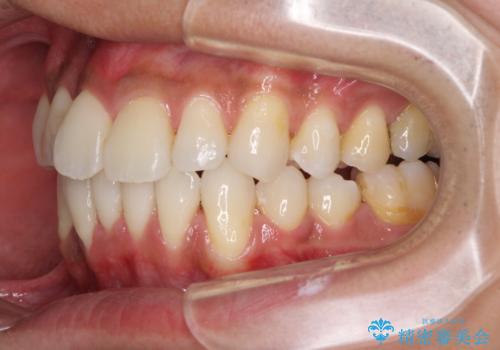

上顎の狭い歯列をインビザラインで拡大

- 上下前歯の叢生を気にして来院された患者様です。

奥歯はクロスバイトとなっているので上顎は側方拡大を行いつつ、上下全体の叢生をインビザラインにより改善することとしました。

治療途中でクリーニングやホワイトニングを行い、歯列が整うと同時に明るい口元となりました。